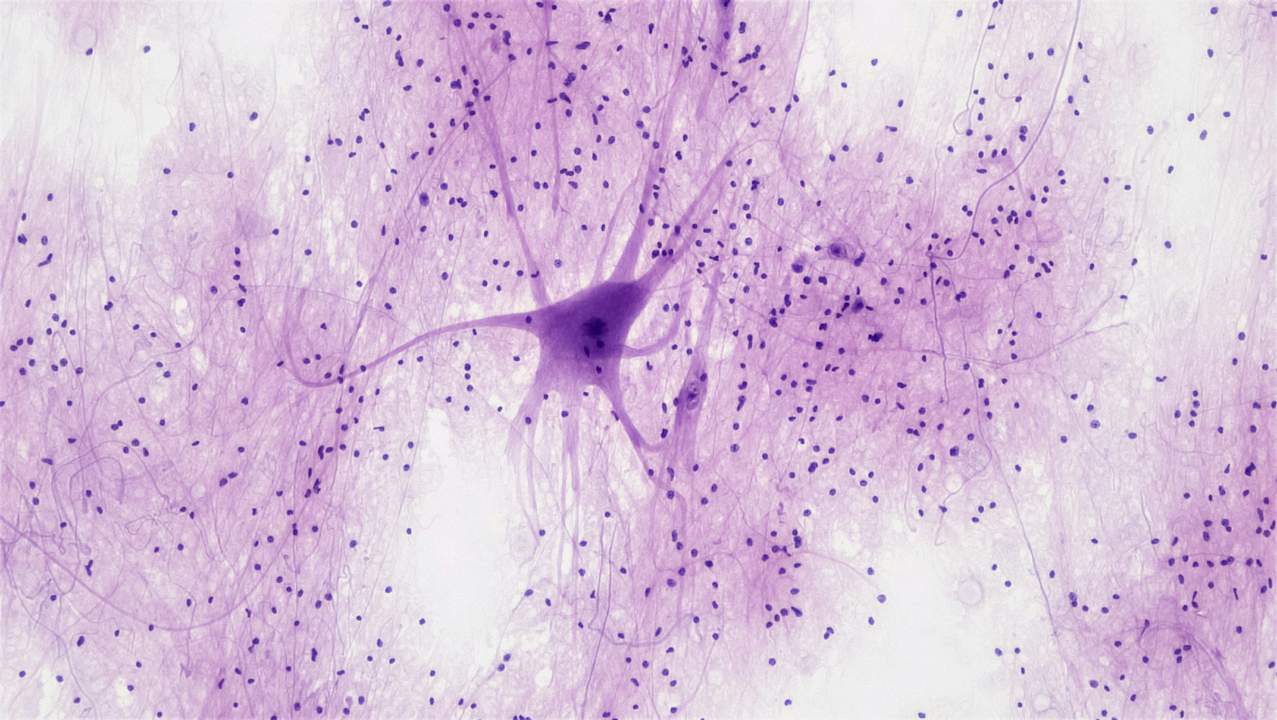

17 juni 2021 door Wetenschap UitgedokterdNa een beroerte hebben veel mensen last van dysfagie, slikproblemen die ontstaan door schade aan hersengebieden die verantwoordelijk zijn voor het regelen van slikproces. Marthe Everaert (KU Leuven) onderzoekt of elektrische stimulatie patiënten kan helpen de controle van de hersenen over het slikken te herstellen.